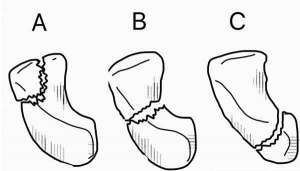

Scaphoid fractures occur in three locations: (A) Distal tubercle, (B) waist, and (C) proximal pole.